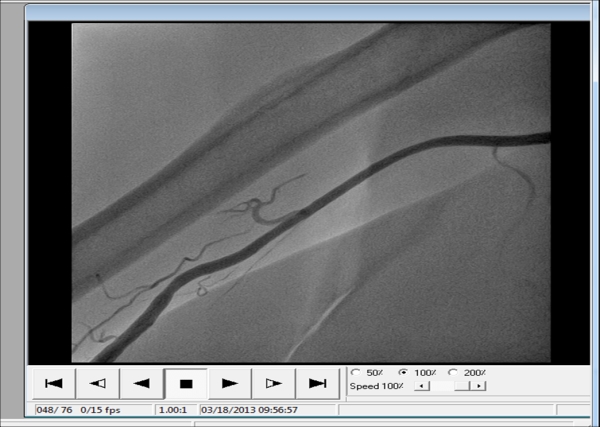

أجريت في مدينة الإمام الحسين (ع) الطبية شعبة قسطرة القلب أول عملية قسطرة تشخيصية لشرايين القلب عن طريق الشريان الكعبري (radial approach teans) الموجود في رسغ اليد بحسب (اختصاص دقيق أمراض القلب)

وقال الدكتور مشتاق طالب لوكالة نون الخبرية "إن هذه العملية تعتبر الأولى من نوعها في كربلاء وهي عملية معقدة لكن تعتبر أسهل للمريض حيث لا يعاني أي مشاكل على الإطلاق ويستطيع المريض مغادرة المستشفى بعد عشرة دقائق من إجرائها بعكس العملية التقليدية التي تجرى عن طريق الشريان الفخذي التي تتطلب من المريض البقاء في المستشفى مدة ست ساعات أو يوم كامل,موضحاً إن هكذا نوع من العمليات تجرى في مراكز محدودة في العراق كمستشفى ابن البيطار ومركز جراحة القلب في الناصرية ,كاشفاً عن إن (15)عملية قسطرة تشخيصية تتم في المستشفى أسبوعيا مؤكدا وجود أربعة أطباء اختصاص قلب في شعبة القسطرة بالإضافة إلى وجود طبيبان اختصاص (جراحة أوعية دموية )وهذا العدد يكفي حالياً لإنشاء مركز لإمراض وجراحة القلب ومحافظة كربلاء بحاجة ماسة إلى المركز كون معظم مرضى المحافظة يضطرون للذهاب إلى المحافظات المجاورة أو خارج العراق لأجرائها مشدداً على إن البرتوكول الخاص بوزارة الصحة والجمعية الأمريكية لأطباء القلب يسمح بإجراء عمليات التداخل القسطاري للحالات الطارئة بدون غطاء جراحي .